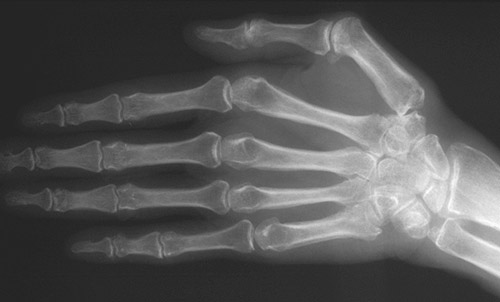

| The hand here shows changes of hypertrophic osteoarthropathy with periosteal new bone formation at the ends of metacarpals and proximal interphalangeal joints of the hands. This phenomenon may be accompanied by "clubbing" with increased soft tissue and edema of the digits. This condition is most often seen with underlying pulmonary malignancies. Rarely, it is a familial phenomenon. |